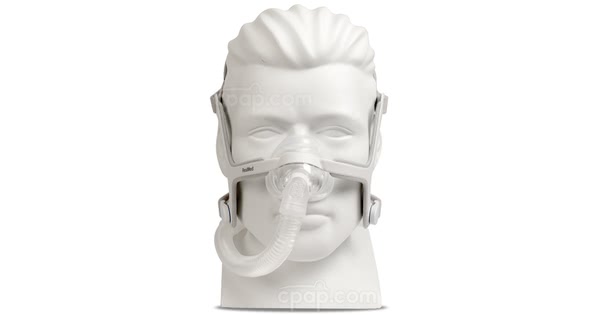

CPAP呼吸機(jī)配有(yǒu)機(jī)器(qì),軟管和(hé)面罩。大(dà)多(duō)數(shù)機(jī)器(qì)很(hěn)小(xiǎ✘o)-大(dà)約隻有(yǒu)紙(zhǐ)巾盒的(de)大(dà)小(xiǎo)-重量輕且相(xiàng)對(duì)安靜(jìng)。您可(kě)以'将CPAP機(jī)器(qì)放(fàng)在床頭櫃上(shàng)或床邊。

管道(dào)将CPAP機(jī)器(qì)連接到(dào)您的(de)面罩。管道(dào)足夠長(cháng)可(kě)以讓您ε在床上(shàng)移動或翻身(shēn)。

CPAP呼吸機(jī)面罩可(kě)能(néng)隻覆蓋您的(de)鼻子(zǐ)或鼻子(zǐ)和(hé)嘴巴。另一(yī)種選擇是(shì)使用(yòng)适合您鼻孔的(≠de)“鼻枕”。無論您使用(yòng)哪種類型的(de)口罩,重要(yào)的(de)是(shì)要(yào)貼合好(hǎo)用(yòng)且舒适。面罩必須密封,以保持通(tōn₽g)氣通(tōng)宵通(tōng)宵。良好(hǎo)的(de)面罩密封将防止空(kōng)氣洩漏并保持适當的(de)氣壓水(sh→uǐ)平。

口罩的(de)種類

CPAP掩碼有(yǒu)三種常見(jiàn)類型。無論您使用(yòng)哪種類型的(de)口罩,重要(yào)的(de)是(shì)要(yào)貼合好(hǎo)用(>yòng)且舒适。

鼻罩

這(zhè)個(gè)面具隻覆蓋你(nǐ)的(de)鼻子(zǐ)。這(zhè)是(shì)CPAP掩碼的(de)最常見∞(jiàn)類型。

面罩

此面膜覆蓋您的(de)鼻子(zǐ)和(hé)嘴巴。如(rú)果您在使用(yòng)鼻罩時(shí)漏氣,這(zhè)種面罩可(¶kě)能(néng)會(huì)有(yǒu)所幫助。

鼻枕

此面罩使用(yòng)可(kě)直接插入鼻子(zǐ)的(de)柔軟矽膠管。如(rú)果您漏氣或不(bù)喜歡鼻子(zǐ)和(hé)臉部戴口罩的(₩de)感覺,這(zhè)可(kě)能(néng)會(huì)有(yǒu)所幫助。